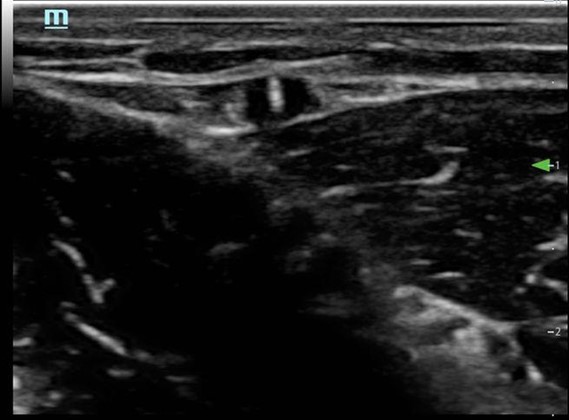

- Follow the needle tip until it enters the vein. (Fig. 4)The needle tip is followed into the lumen of the vessel. It is essential that the transducer is advanced before the needle tip so as not to mistake the needle shaft for the tip and risk potential damage to the posterior wall of the vessel. Advance the needle tip in conjunction with the transducer for 1-2 cm additionally to ensure enough of the catheter is in the vessel.3 (Fig. 5)

Figure 4. Short axis approach: Entering the vessel